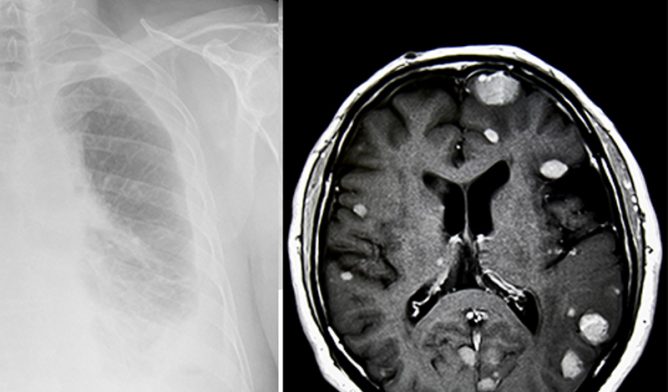

Mesothelioma in lung and brain tumors

Brain metastasis is rare, even for pleural mesothelioma’s final stages, but it does occur. A 2017 study published in the Journal of Clinical Oncology shows that only 3% of mesothelioma cases spread to the brain.

In a 2017 case report published in the Journal of Neurology, Neurological Science and Disorders, a 66-year-old man developed slurred speech and drooping on the right side of his face 1 1/2 years after undergoing surgery and chemotherapy for pleural mesothelioma. An MRI revealed two masses on the left side of his brain.

He underwent a successful surgery to remove the tumors. In addition, he received post-surgical fractionated gamma knife radiosurgery, which is a type of radiation therapy delivered after the patient has recovered from surgery to kill any remaining cancer cells. The patient was doing well three months later with no recurrence.